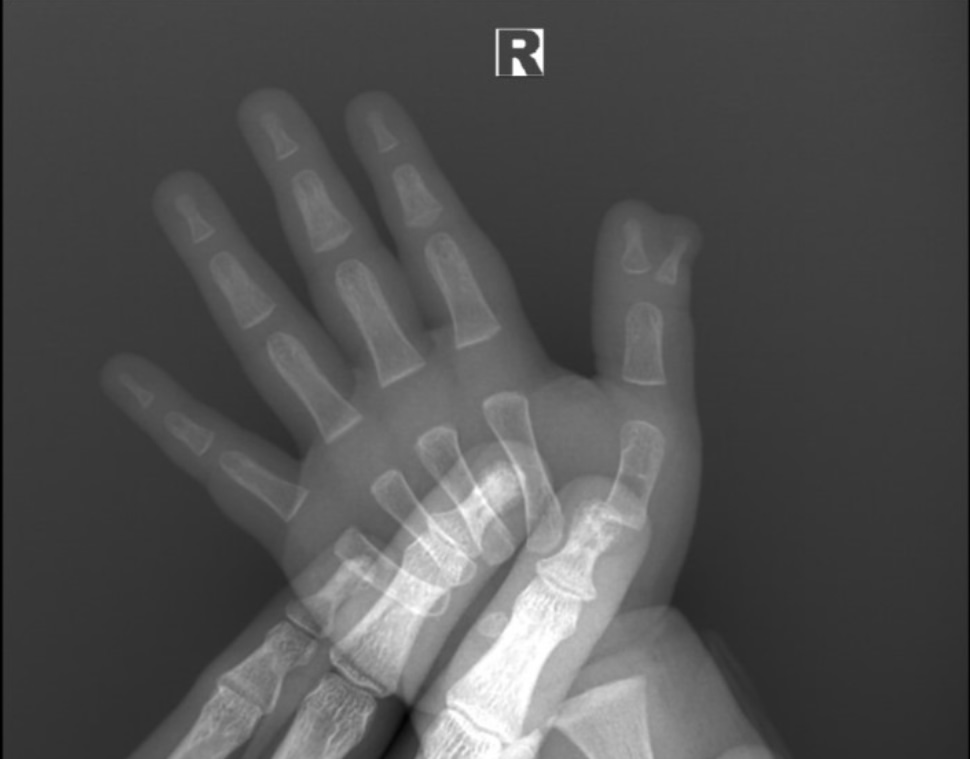

На этот раз в Пигановский центр обратились родители 1,5-летнего ребенка, появившегося на свет с дополнительной ногтевой фалангой большого пальца. Травматологом-ортопедом было назначено оперативное вмешательство для коррекции патологии.